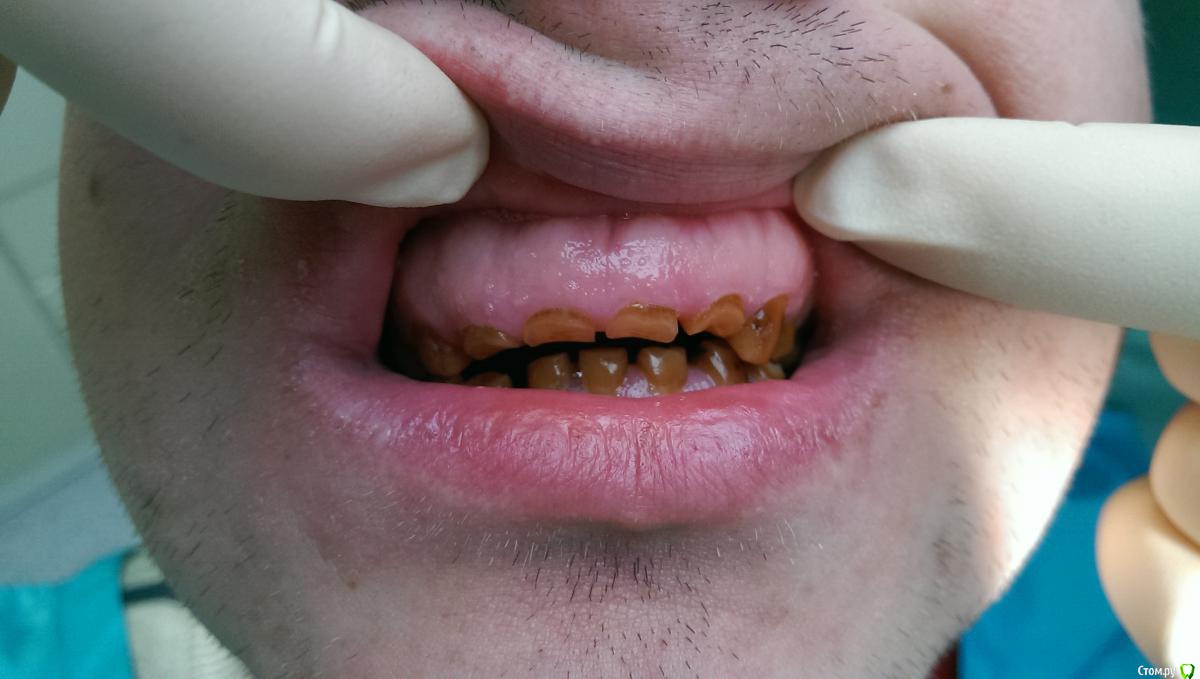

Ром@н Опубликовано 17 декабря, 2014 Поделиться Опубликовано 17 декабря, 2014 Пациент- молодой человек 28 лет.Посоветуйте пожалуйста как быть. Сегодня сфотографировал. ОПТГ будет позже - не знаю только когда, т.к. проподает. Сегодня удалили 1.6. Ссылка на комментарий

Ром@н Опубликовано 17 декабря, 2014 Автор Поделиться Опубликовано 17 декабря, 2014 Вот фото с телефона правда Ссылка на комментарий

DR.P Опубликовано 19 декабря, 2014 Поделиться Опубликовано 19 декабря, 2014 (изменено) Интересный случай. Напишу краткий протокол лечения и варианты:1) измеряем физ покой, и высоту его прикуса. Если разница этих значений больше 2-3 мм - стираемость - необходимо повышать прикус.2) Если 2-3 мм - значит стираемость компенсаторная, то есть с зубоальвеолярным выдвижением. В случае 1) культевые вкладки и коронки (необходимо вернуть высоту прикуса)В случае 2) хирургическое удлинение зубов, коронки Изменено 19 декабря, 2014 пользователем DR.P Ссылка на комментарий

chervoncevdaniil Опубликовано 21 декабря, 2014 Поделиться Опубликовано 21 декабря, 2014 Мне кажется тут явно снижение высоты прикуса компенсировано,взгляните на мощный альвеолярный отросток.Не простая ситуация у пациента,без грамотной хирургии будет сложно Ссылка на комментарий